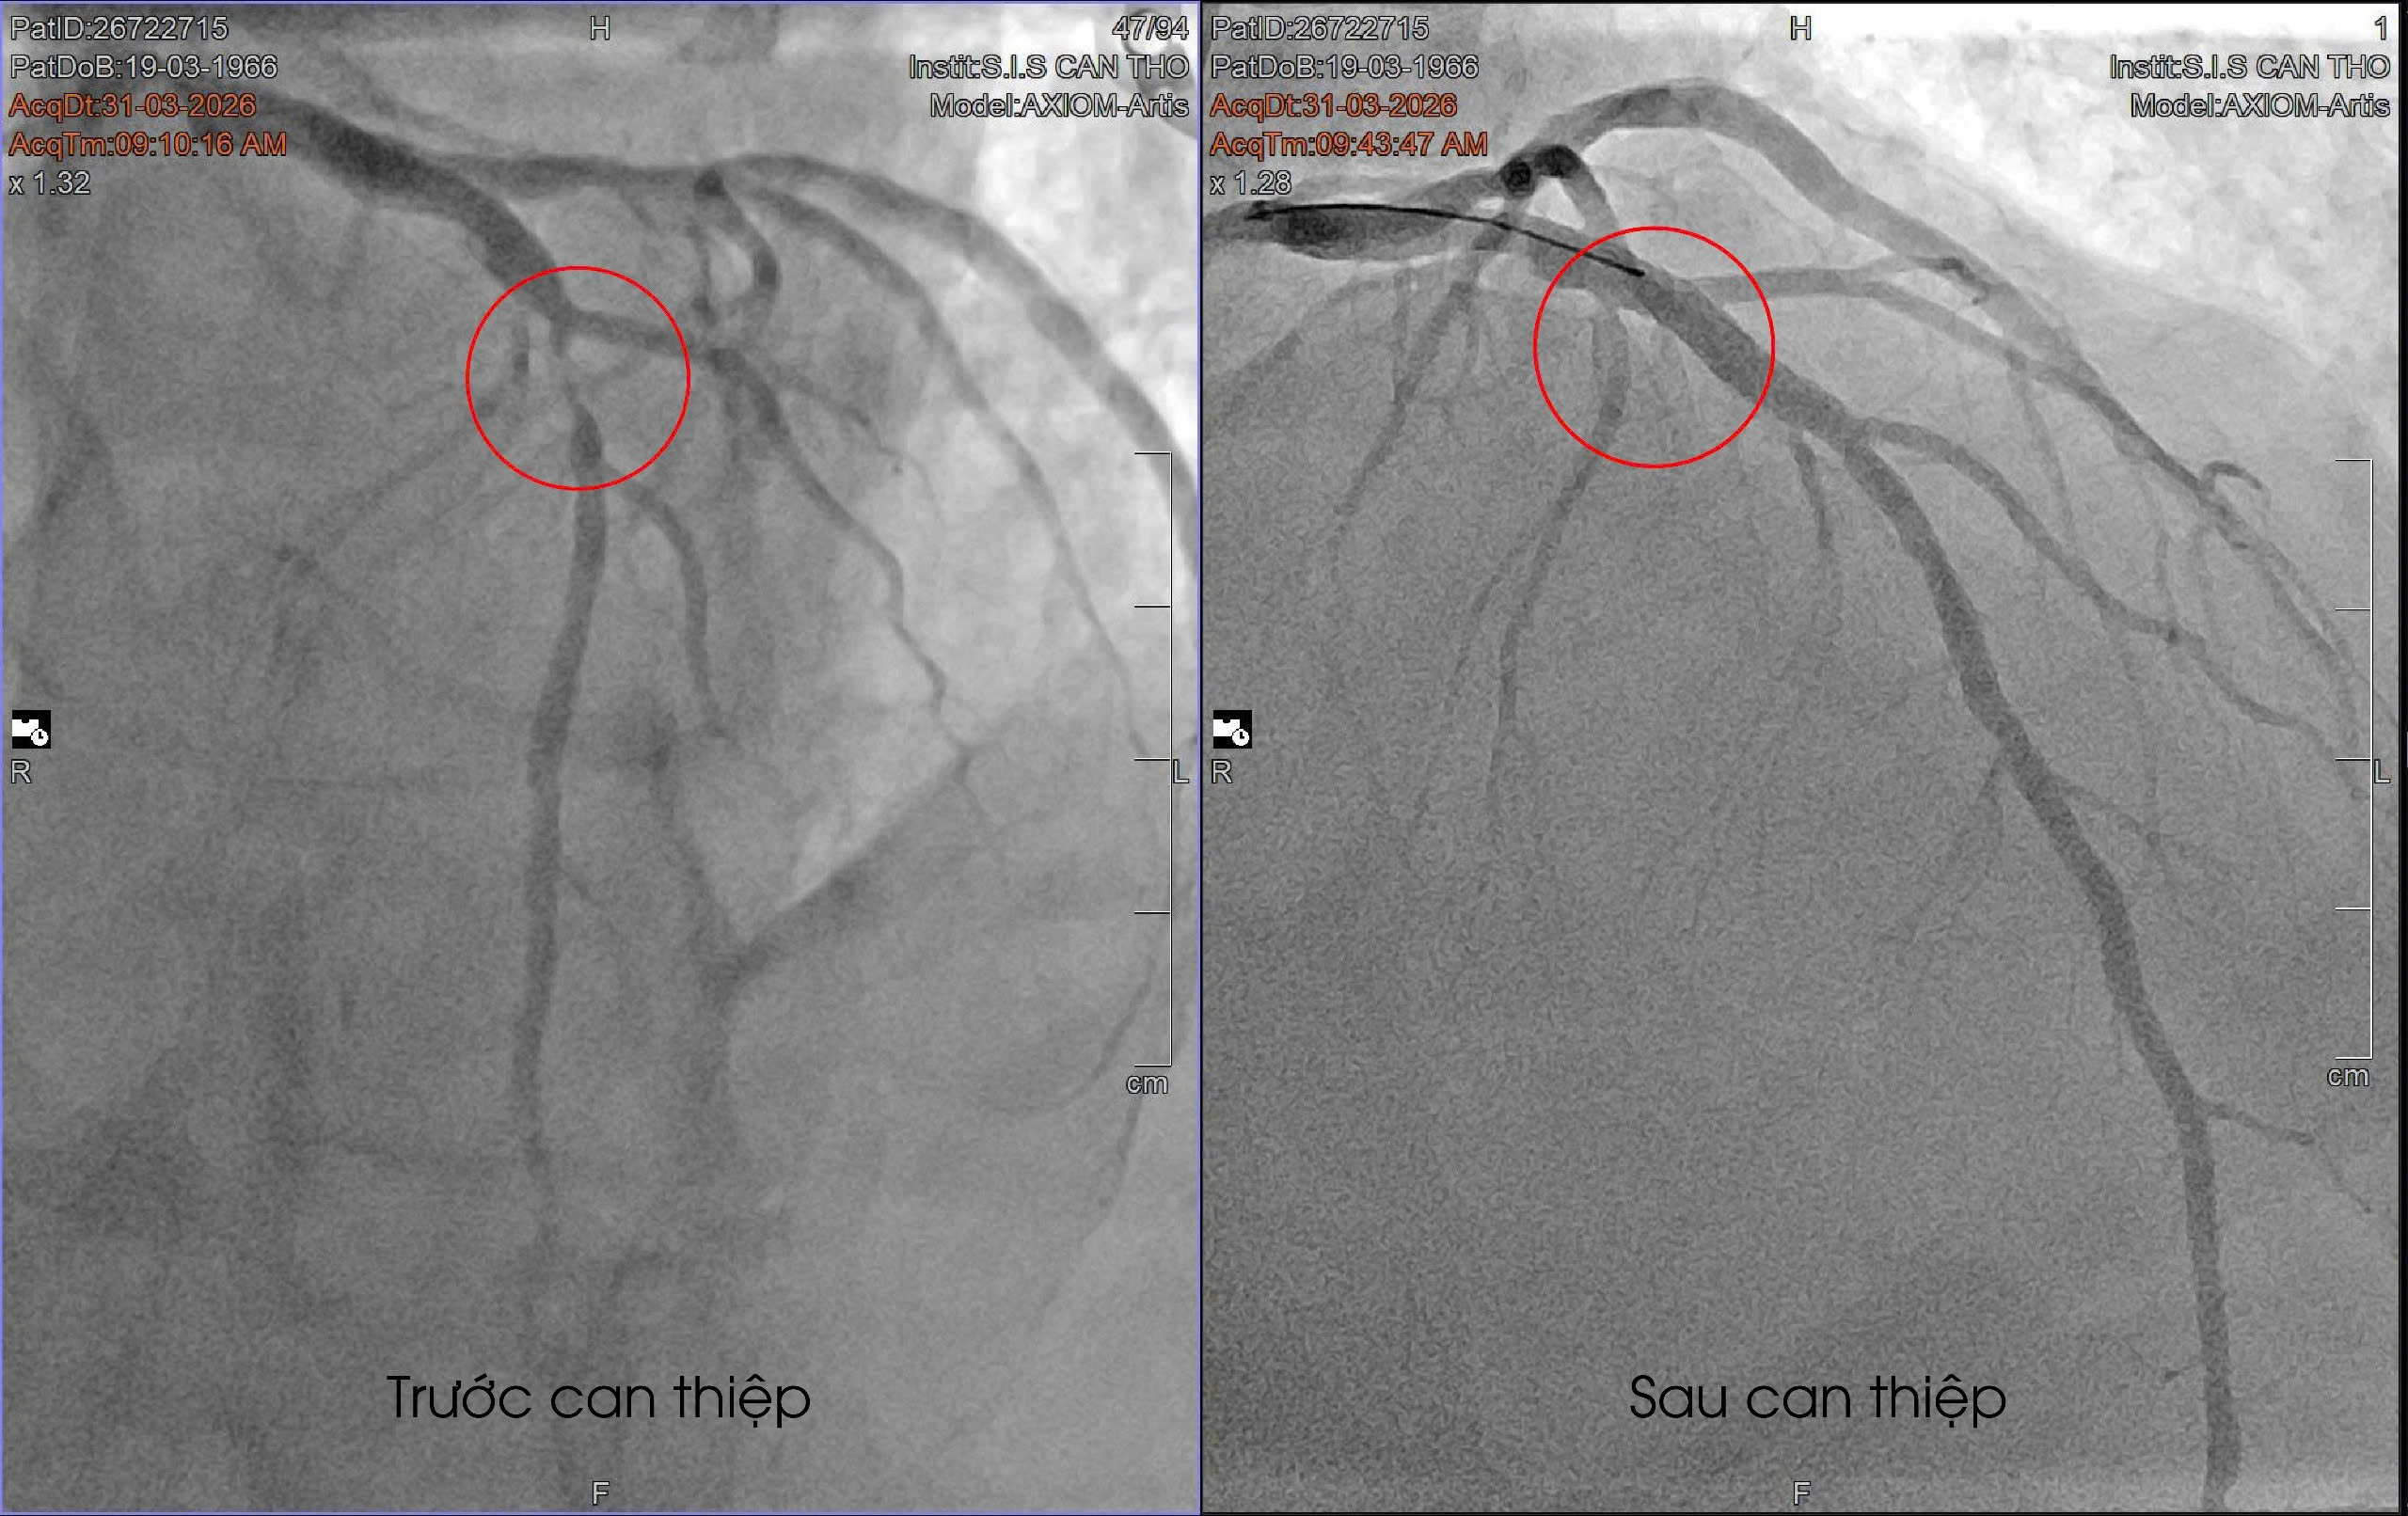

Kết quả chụp mạch vành cho thấy động mạch liên thất trước - mạch máu nuôi phần lớn cơ tim bị hẹp nặng, gần như tắc hoàn toàn. Đây là nhánh mạch đặc biệt quan trọng, chi phối khoảng 50-60% khối cơ tim, nên nếu tắc hoàn toàn có thể dẫn đến đột tử bất cứ lúc nào.

May mắn, dòng máu tại vị trí hẹp vẫn còn lưu thông rất nhỏ, giúp bệnh nhân chưa rơi vào biến chứng nặng. Ê-kíp đã tiến hành can thiệp đặt stent kịp thời. Sau can thiệp, các triệu chứng cải thiện rõ rệt, bệnh nhân hết đau ngực, không còn khó thở và nhanh chóng hồi phục, có thể sinh hoạt bình thường.